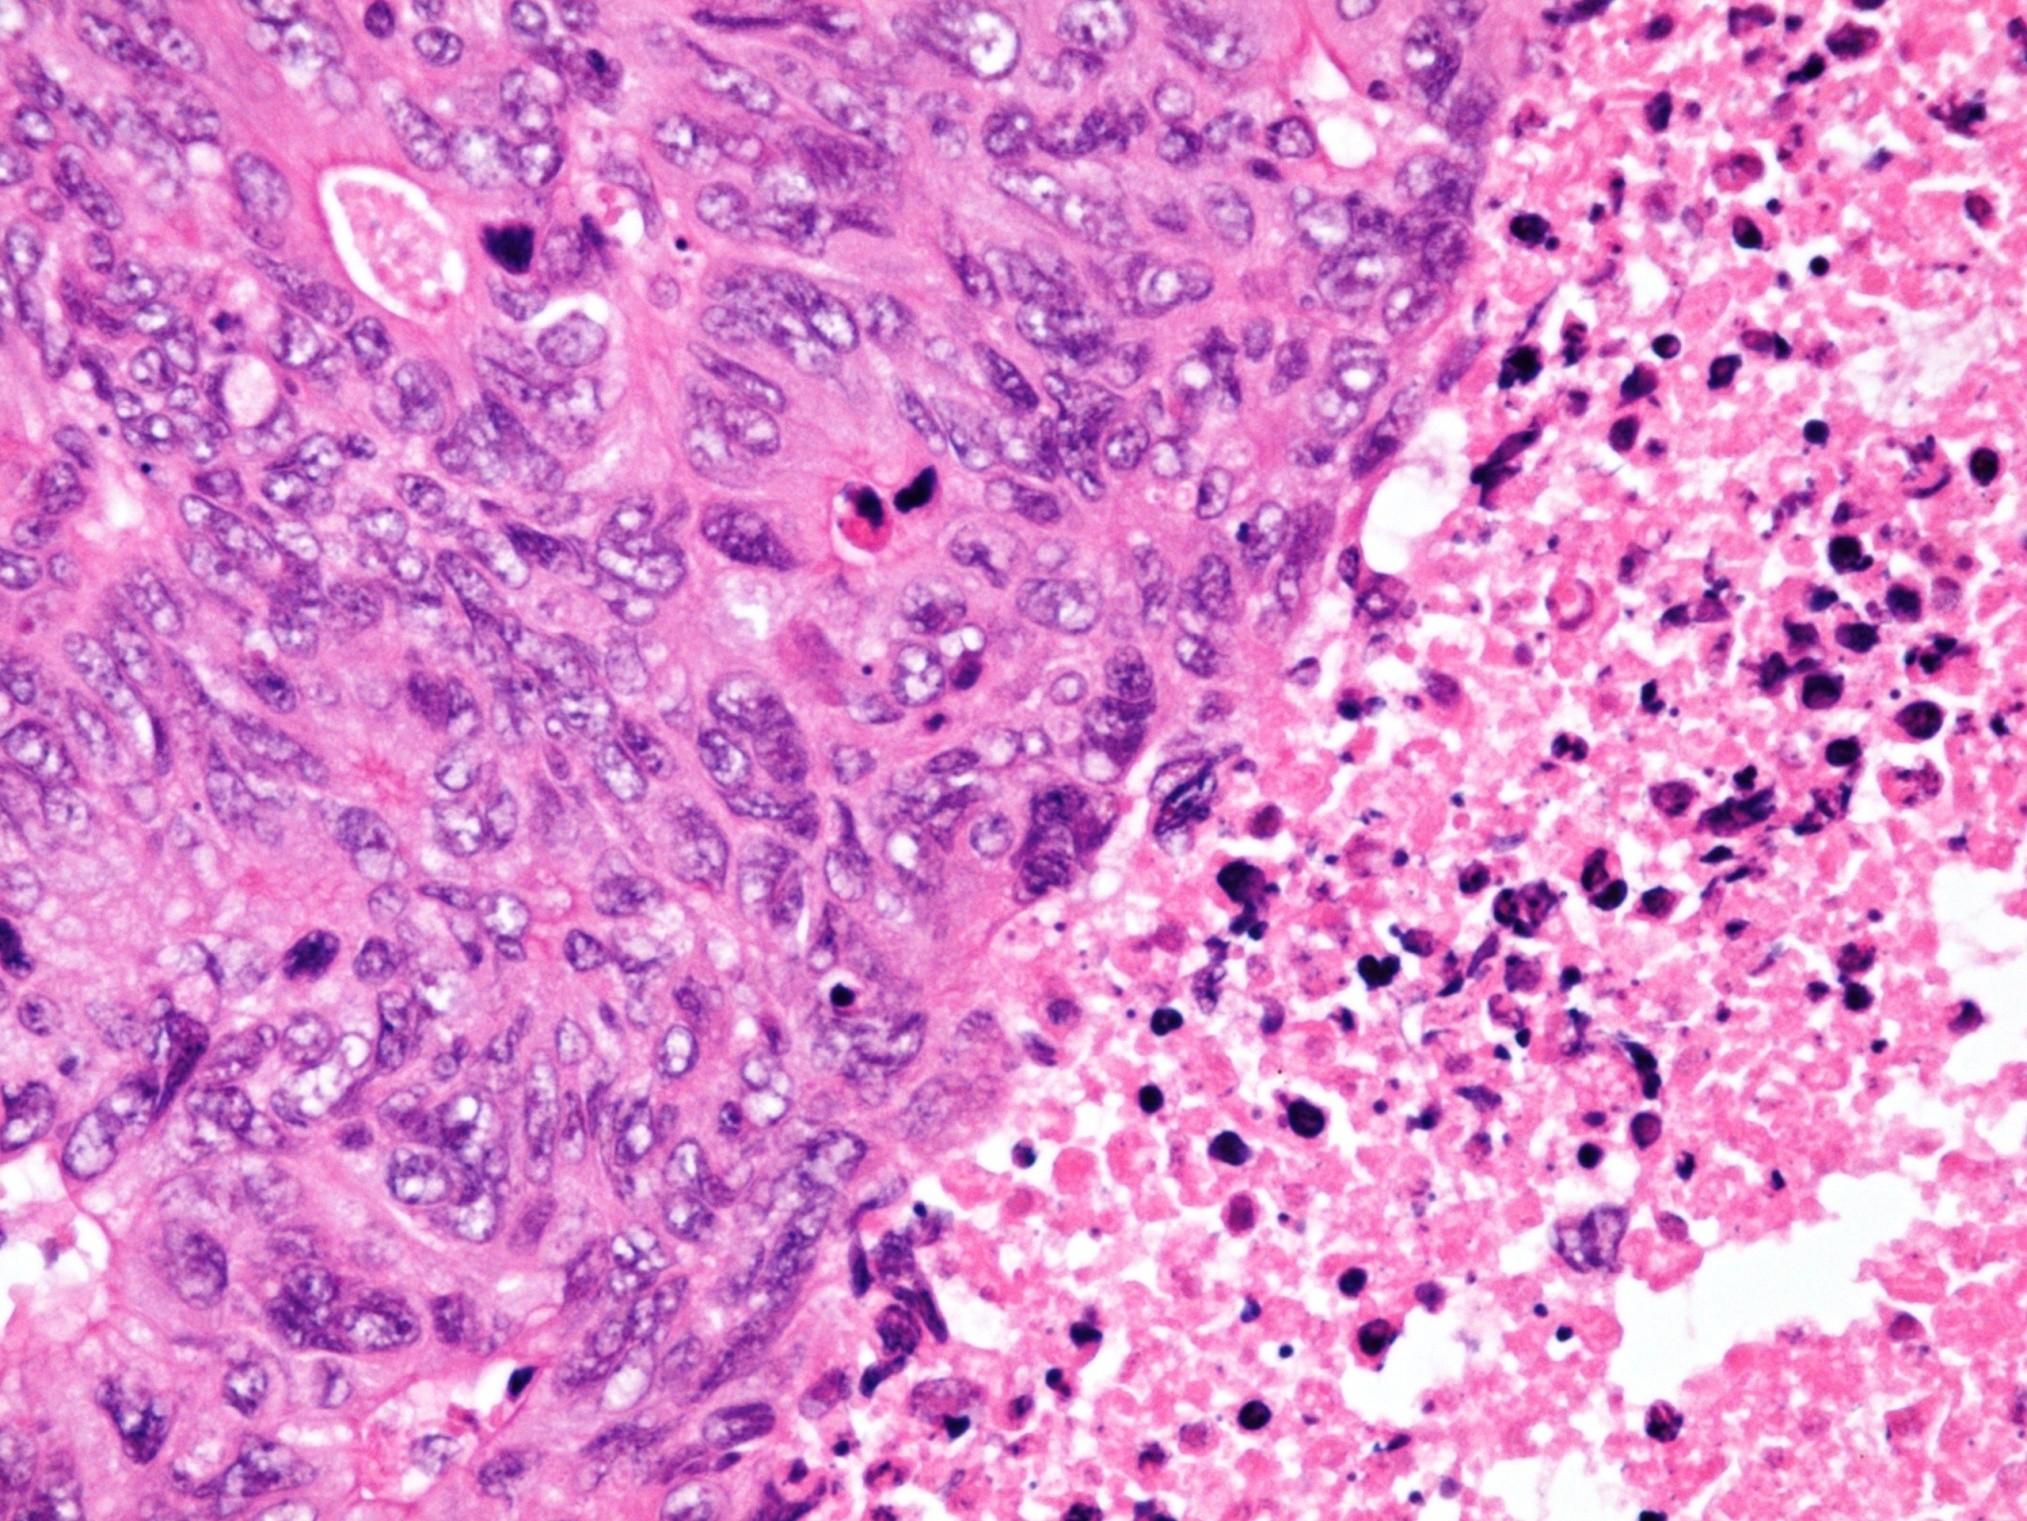

Sinonasal NK/T cell lymphoma

 Broad morphological spectrum

 Polymorphic with atypical lymphoid cells

 Plus background of other cells (neuts eos)

 Pale to clear cytoplasm

 Angioinvasion

 Geographic necrosis

 CD56, variable for T cell markers (CD2)

 EBV related

a, Proliferation of small to large, pleomorphic lymphoma cells

b, Lymphoma cells are invading a vein (arrows)

d, Expression of EBER1 in nuclei of lymphoma cells (EBER in situ hybridization,) Biopsy findings for the nasopharynx prior to radiotherapy.

c, Positive reactions for UCHL-1 are evident on the cytoplasmic membranes of lymphoma cells